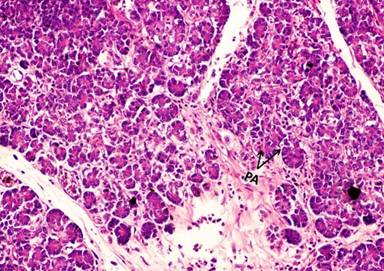

During the regular dissection classes for medical undergraduates, we came across a rare type of congenital anomaly of the annular pancreas. It was observed in an approximately 55-year-old male cadaver of South Indian origin. An apparently normal sized pancreas was situated across the posterior abdominal wall. It had presented classical parts; head, body and tail. Head was situated within the concavity of the duodenum and uncinate process, arising from its inferior border which was smaller than the normal. There was an extra pancreatic mass situated horizontally immediately above the superior border of the pancreas, behind the lesser omentum (Figure 1). The right end of this mass extended towards the epiploic foramen and incompletely encircled the portal vein, bile duct and hepatic artery proper from behind. At the level of epiploic foramen, the mass was found to be continuous with the head of the pancreas (Figures 2 and 3). The left end of the extra pancreatic mass extended towards the lesser curvature of the stomach (Figure 1). This mass completely surrounded the origin of three branches of the celiac trunk. Further, the left gastric artery coursed through the substance of this mass on its way to the cardiac end of the stomach (Figure 1). The initial segment of the splenic artery was found in the gap between the extra pancreatic mass and superior border of body of the normal pancreas. No other associated anomalies were observed in the supracolic compartment of the abdomen. Histology of the extra pancreatic mass revealed the presence of classical pancreatic lobules with serous acini, similar to the native pancreas (Figure 4).

Figure 4. Histology of extra pancreatic mass showing the pancreatic tissue with classical lobular arrangement. Note the pancreatic serous acini (PA) in the lobule. (H&E staining, 10x magnification). |